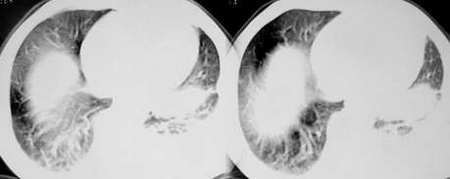

以下是引用sdqzwyx在2005-11-7 19:59:00的发言:[br]双肺弥漫大小不等的粟粒状结节影;肺纹理走行失去自然,粗细不均,边缘不规则,小叶间隔增厚;左上肺示不规则形致密影,从斑块边缘向周围伸出长短不一的致密索条影,临近的血管、支气管和叶间胸膜等结构受牵拉移位;左下肺示不规则团块状影,其内示空洞,洞内壁尚光整,左侧胸腔积液。右肺下叶背段亦示部分病灶融合。双肺可见局限性肺气肿。[br]诊断:结合病史符合三期矽肺表现(少数矽肺纤维斑块内可以形成空洞,一般认为是斑块中央感染引起坏死所致)但尘肺病人易合并肺结核,诊断可为三期+tb。所以此病人应进一步检查是否合并结核。